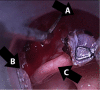

Often discovered only after an extensive work up for hemoptysis and hematemesis, vallecular varices are a rare cause of oral bleeding that increase patient morbidity due to delay of diagnosis. We describe an 89-year-old male who presented with a week of intermittent oral blood production. A vallecular varix was identified on fiberoptic laryngoscopy after studies for hematemesis and hemoptysis had been performed, including negative esophagogastroduodenoscopy and bronchoscopy. Awareness of this pathology and key points in the patient history can direct the clinician toward the correct diagnosis, expediting treatment and limiting invasive diagnostic procedures for pulmonary or gastric etiologies of bleeding.